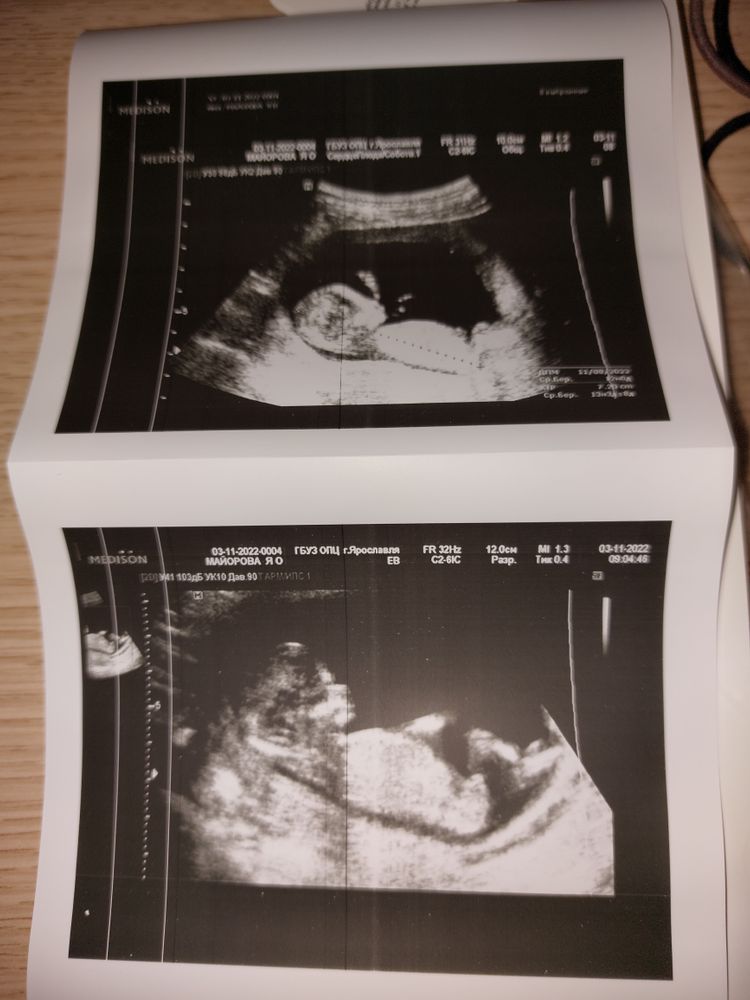

Сегодня в 12 недель был первый скриниг и мы наконец-то познакомились с нашим малышом 🥰 Сказали, что мальчик 101%, но мы и не сомневались, потому что знали , что так и есть(было много чудесных подтверждений)